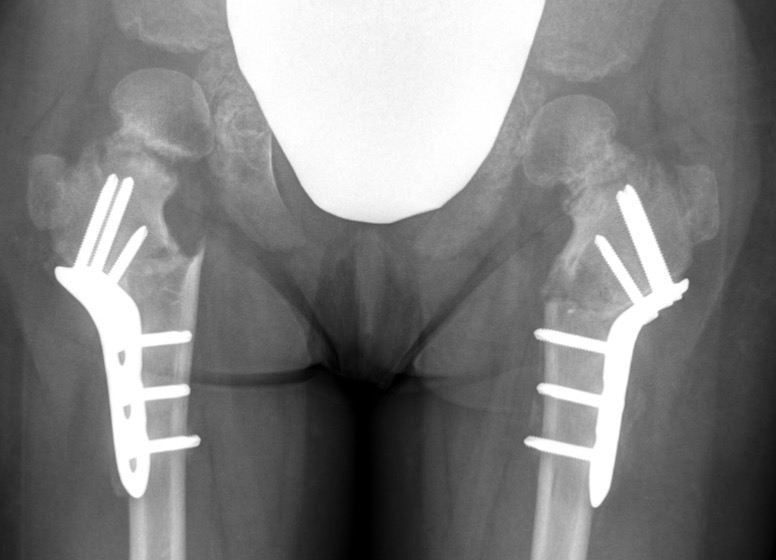

Operative management

Valgus derotation subtrochanteric osteotomy

- overcorrect to 150˚

- epiphyseal angle < 40o

- correct anteversion to 10o

Technique

Synthes Pediatric Proximal Femur Offset Plate Technique PDF

POSA proximal femoral osteotomy for coxa vara video

Lateral approach

- elevate / L shaped detachment of vastus lateralis

- mark distal and proximal with drill hole for rotation

- K wire in central head

- sub-trochanteric osteotomy with saw

- application of 150o Synthes offset locking plate

- internal rotation of about 20° at time of osteotomy

May require

- adductor tenotomy

- femoral shortening

- greater torchanter transfer